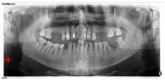

Background: This study sought to determine the prevalence of carotid artery calcifications (CACs) and pulp stones detected on panoramic radiographs (PRs) and ascertain their correlation.

Methods: A total of 2013 digital PRs were retrospectively retrieved and thoroughly examined to determine the prevalence of CACs and pulp stones, their correlation with patient age and gender, and the relationship between the presence of pulps stones and radiographically detectable CACs.

Results: The prevalence of CACs on PRs was 2.0%; the prevalence of pulp stones was 4.6%. There was no statistical relationship between pulp stones and CACs (p = 0.714). Older patients exhibited a significantly higher prevalence of CACs than younger patients (p < 0.001); pulp stones were statistically more prevalent in younger patients than older patients (p = 0.001). There were no significant differences between male and females in terms of the prevalence of either CACs or pulp stones (p = 0.087 and p = 0.278, respectively).

Conclusions: Dentists should be trained to detect CACs on PRs belonging to patients older than 40 to exclude the presence of CACs. Moreover, pulp stones do not function as a diagnostic marker for CACs.